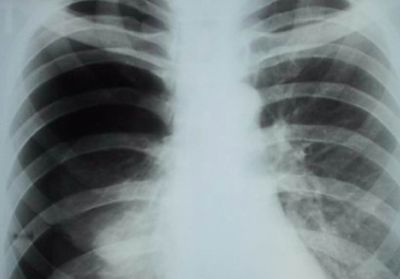

Пневмония

Характер и локализация боли

Правостороннее воспаление легкого характеризуется тупой болью в правом боку, локализованной преимущественно в подреберье.

При длительном течении заболевания боль ощущается в груди и спине со стороны пораженного органа.

Диагностика и лечение

При возникновении описанных выше симптомов необходимо обратиться к пульмонологу, который проведет осмотр и сбор анамнеза и назначит дополнительные диагностические процедуры, включающие:

- рентгенографию;

- КТ;

- фибробронхоскопию;

- клинические, биохимические и бактериологические исследования крови и отделяемой мокроты.